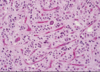

Glioblastoma multiforme

Pseudopallisading necrosis and microvascular proliferation

Ring enhancing - due to breakdown of BBB